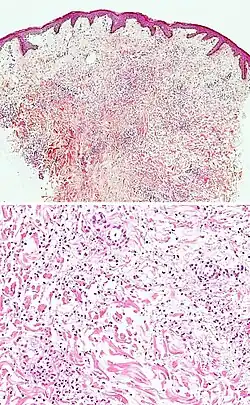

| Pigmented purpuric dermatosis |

|